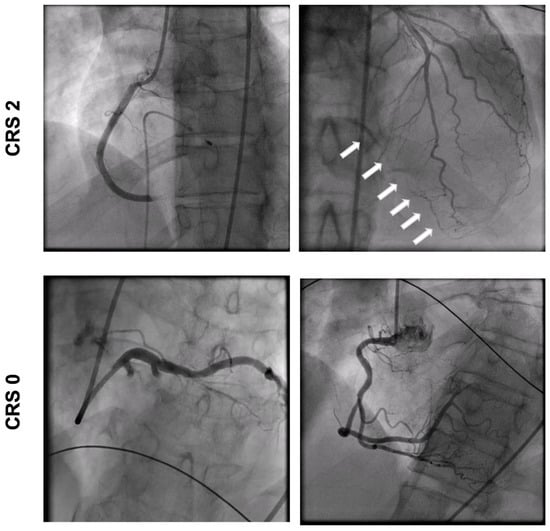

2.2. Coronary Angiography

| Culprit vessel | <0.001 | |||

| LAD, n (%) | 14 (39) | 14 (50) | 0 | |

| LCX, n (%) | 9 (25) | 9 (32) | 0 | |

| RCA, n (%) | 13 (36) | 5 (18) | 8 (100) | |